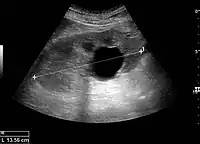

Figure 15. End-stage hydronephrosis with cortical thinning. Measurement of pelvic dilatation on the US image is illustrated by ‘+’ and a dashed line.[1]

Figure 16. Hydronephrosis with dilated anechoic pelvis and calyces, along with cortical atrophy. The width of a calyx is measured on the US image in the longitudinal scan plane, and illustrated by ‘+’ and a dashed line.[1]

Figure 17. Same patient as in Figure 16 with measurement of the pelvis dilation in the transverse scan plane illustrated on the US image with ‘+’ and a dashed line.[1]